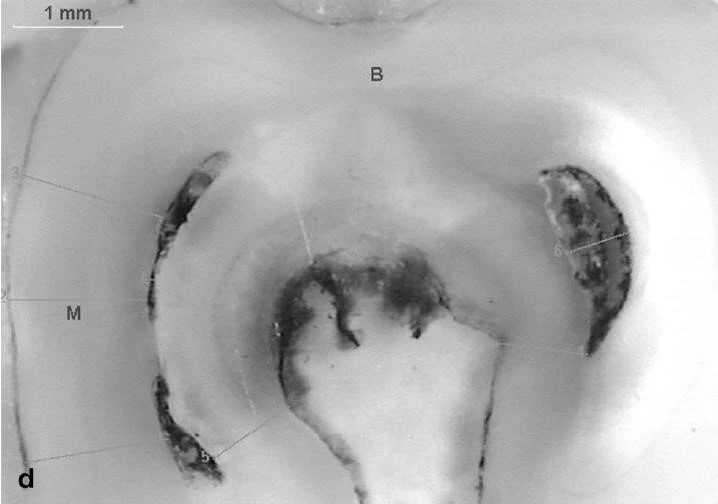

Có nhiều cách phân loại ,nhưng tôi thấy cách phân loại theo Wen Lin Chai,Yo Len Thong thuộc đại học Malaysia đăng trên Journal of Endodontic Vol .30.No .7 ,July 2004 là khá đơn giản ,các tác giả này đã phân CS thành 4 loại :

Theo một khảo sát trên 20 cases CS ,thì tỷ lệ : loại 1 là 27%,2+3 là 64%,loại 4 là 9%. Trong đó 95% là Răng 7 hàm dưới .Theo một số báo cáo khác thì CS cũng gặp trên R6 dưới,R4 dưới,R8 dưới,R6 trên,R7 trên.Lưu ý là phân loại này chỉ tính trên lỗ ống tủy ( orifices) tại sàn buồng tủy chứ còn nếu xuống theo từng lát cắt ngang ( cross – section) thì nó có thể biến từ dạng này sang dạng khác ( khi dính,khi lại tách rời !).

Hình ảnh một ÔT được OB bằng Thermafil+ GP lỏng ( nguồn : GUTMANN).